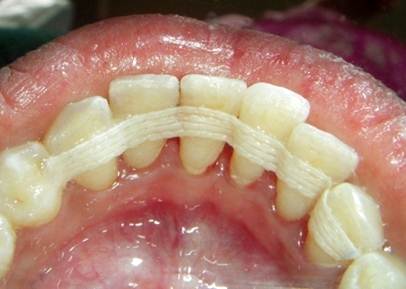

Periodontal splinting is a process by which loose teeth are stabilized by splinting them to adjoining teeth, much in the same way a sprained or broken finger will be splinted to one of the fingers next to it in order to be held secure and heal properly. The periodontal splint is typically made of fibrous composite material and can be very effective at holding teeth in place and saving them from extraction. A periodontal splint can be affixed to your teeth in your dentist's office and typically does not require anesthesia.

1. Extra-coronal Splints("extra" - outside: "coronal" - crown): With this approach, splinting materials are attached to a group of teeth generally by bonding to the enamel, thus making them more rigid.